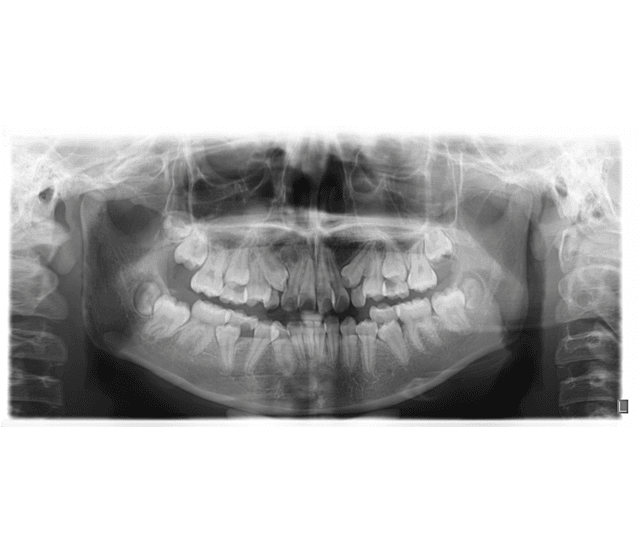

X-Rays

clinic use the latest x-ray technology to diagnose oral health problems in a painless, non-invasive way. Though exposure to radiation can pose health risks, uses sophisticated, portable x-rayuses sophisticated, portable x-ray